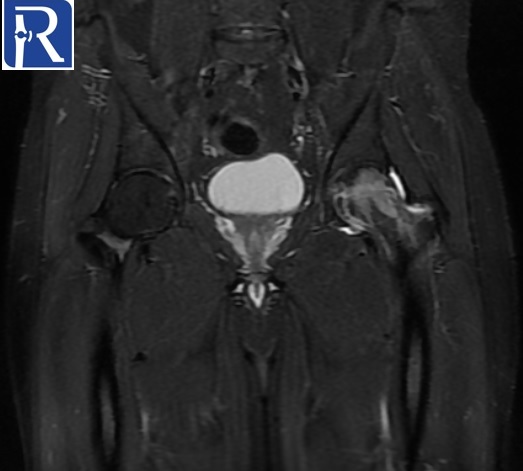

Image Details: AP X-Ray shows the diffuse decrease in density of left proximal femur, suggesting the osteopenia of left proximal femur. MR images shows the edema like signal changes in neck and head of left femur. Mild amount of effusion is present in left joint. Radiological (bone marrow edema and osteopenia of proximal femur) and clinical (young adult male with unilateral hip pain) suggest the diagnosis of transient osteoporosis of hip.